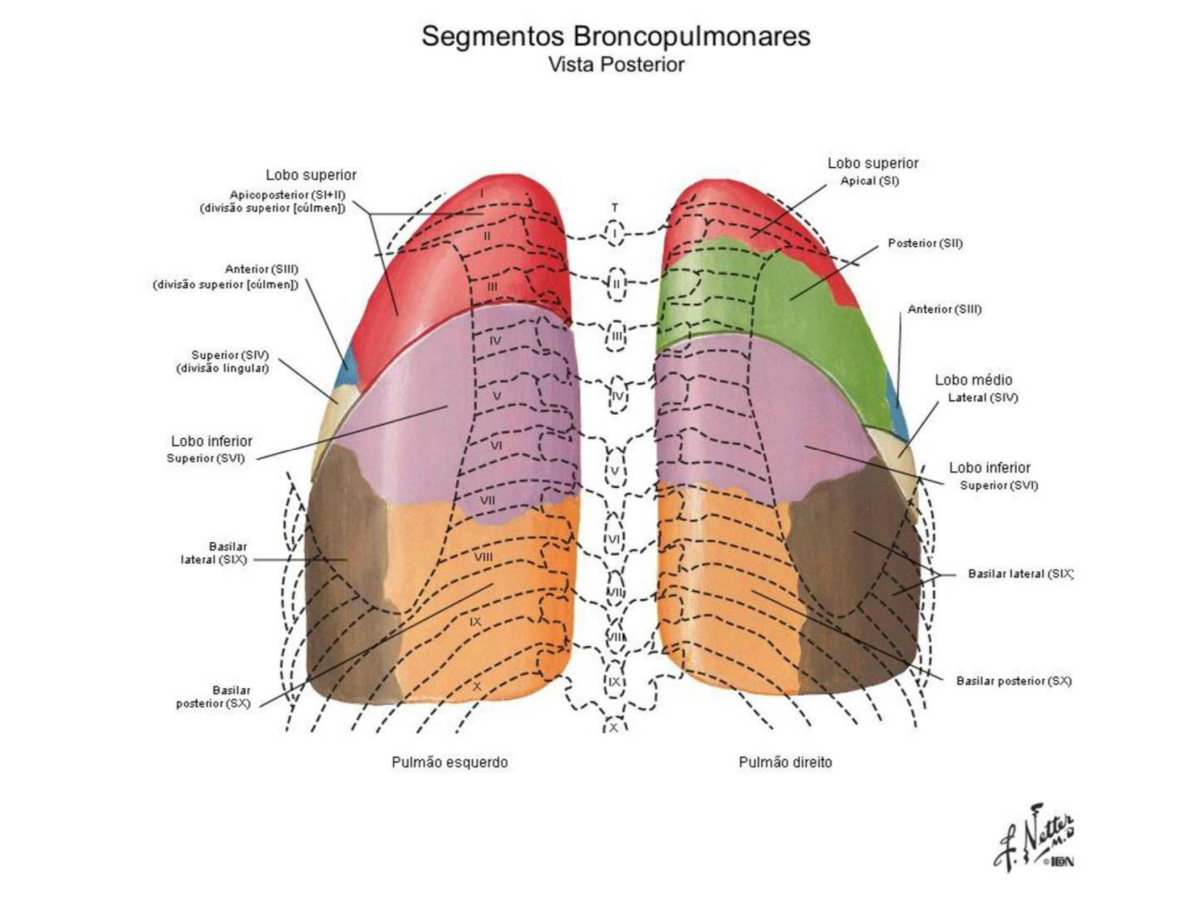

Анатомические изображения сегментов легких различных животных

Раздел: Другие животные